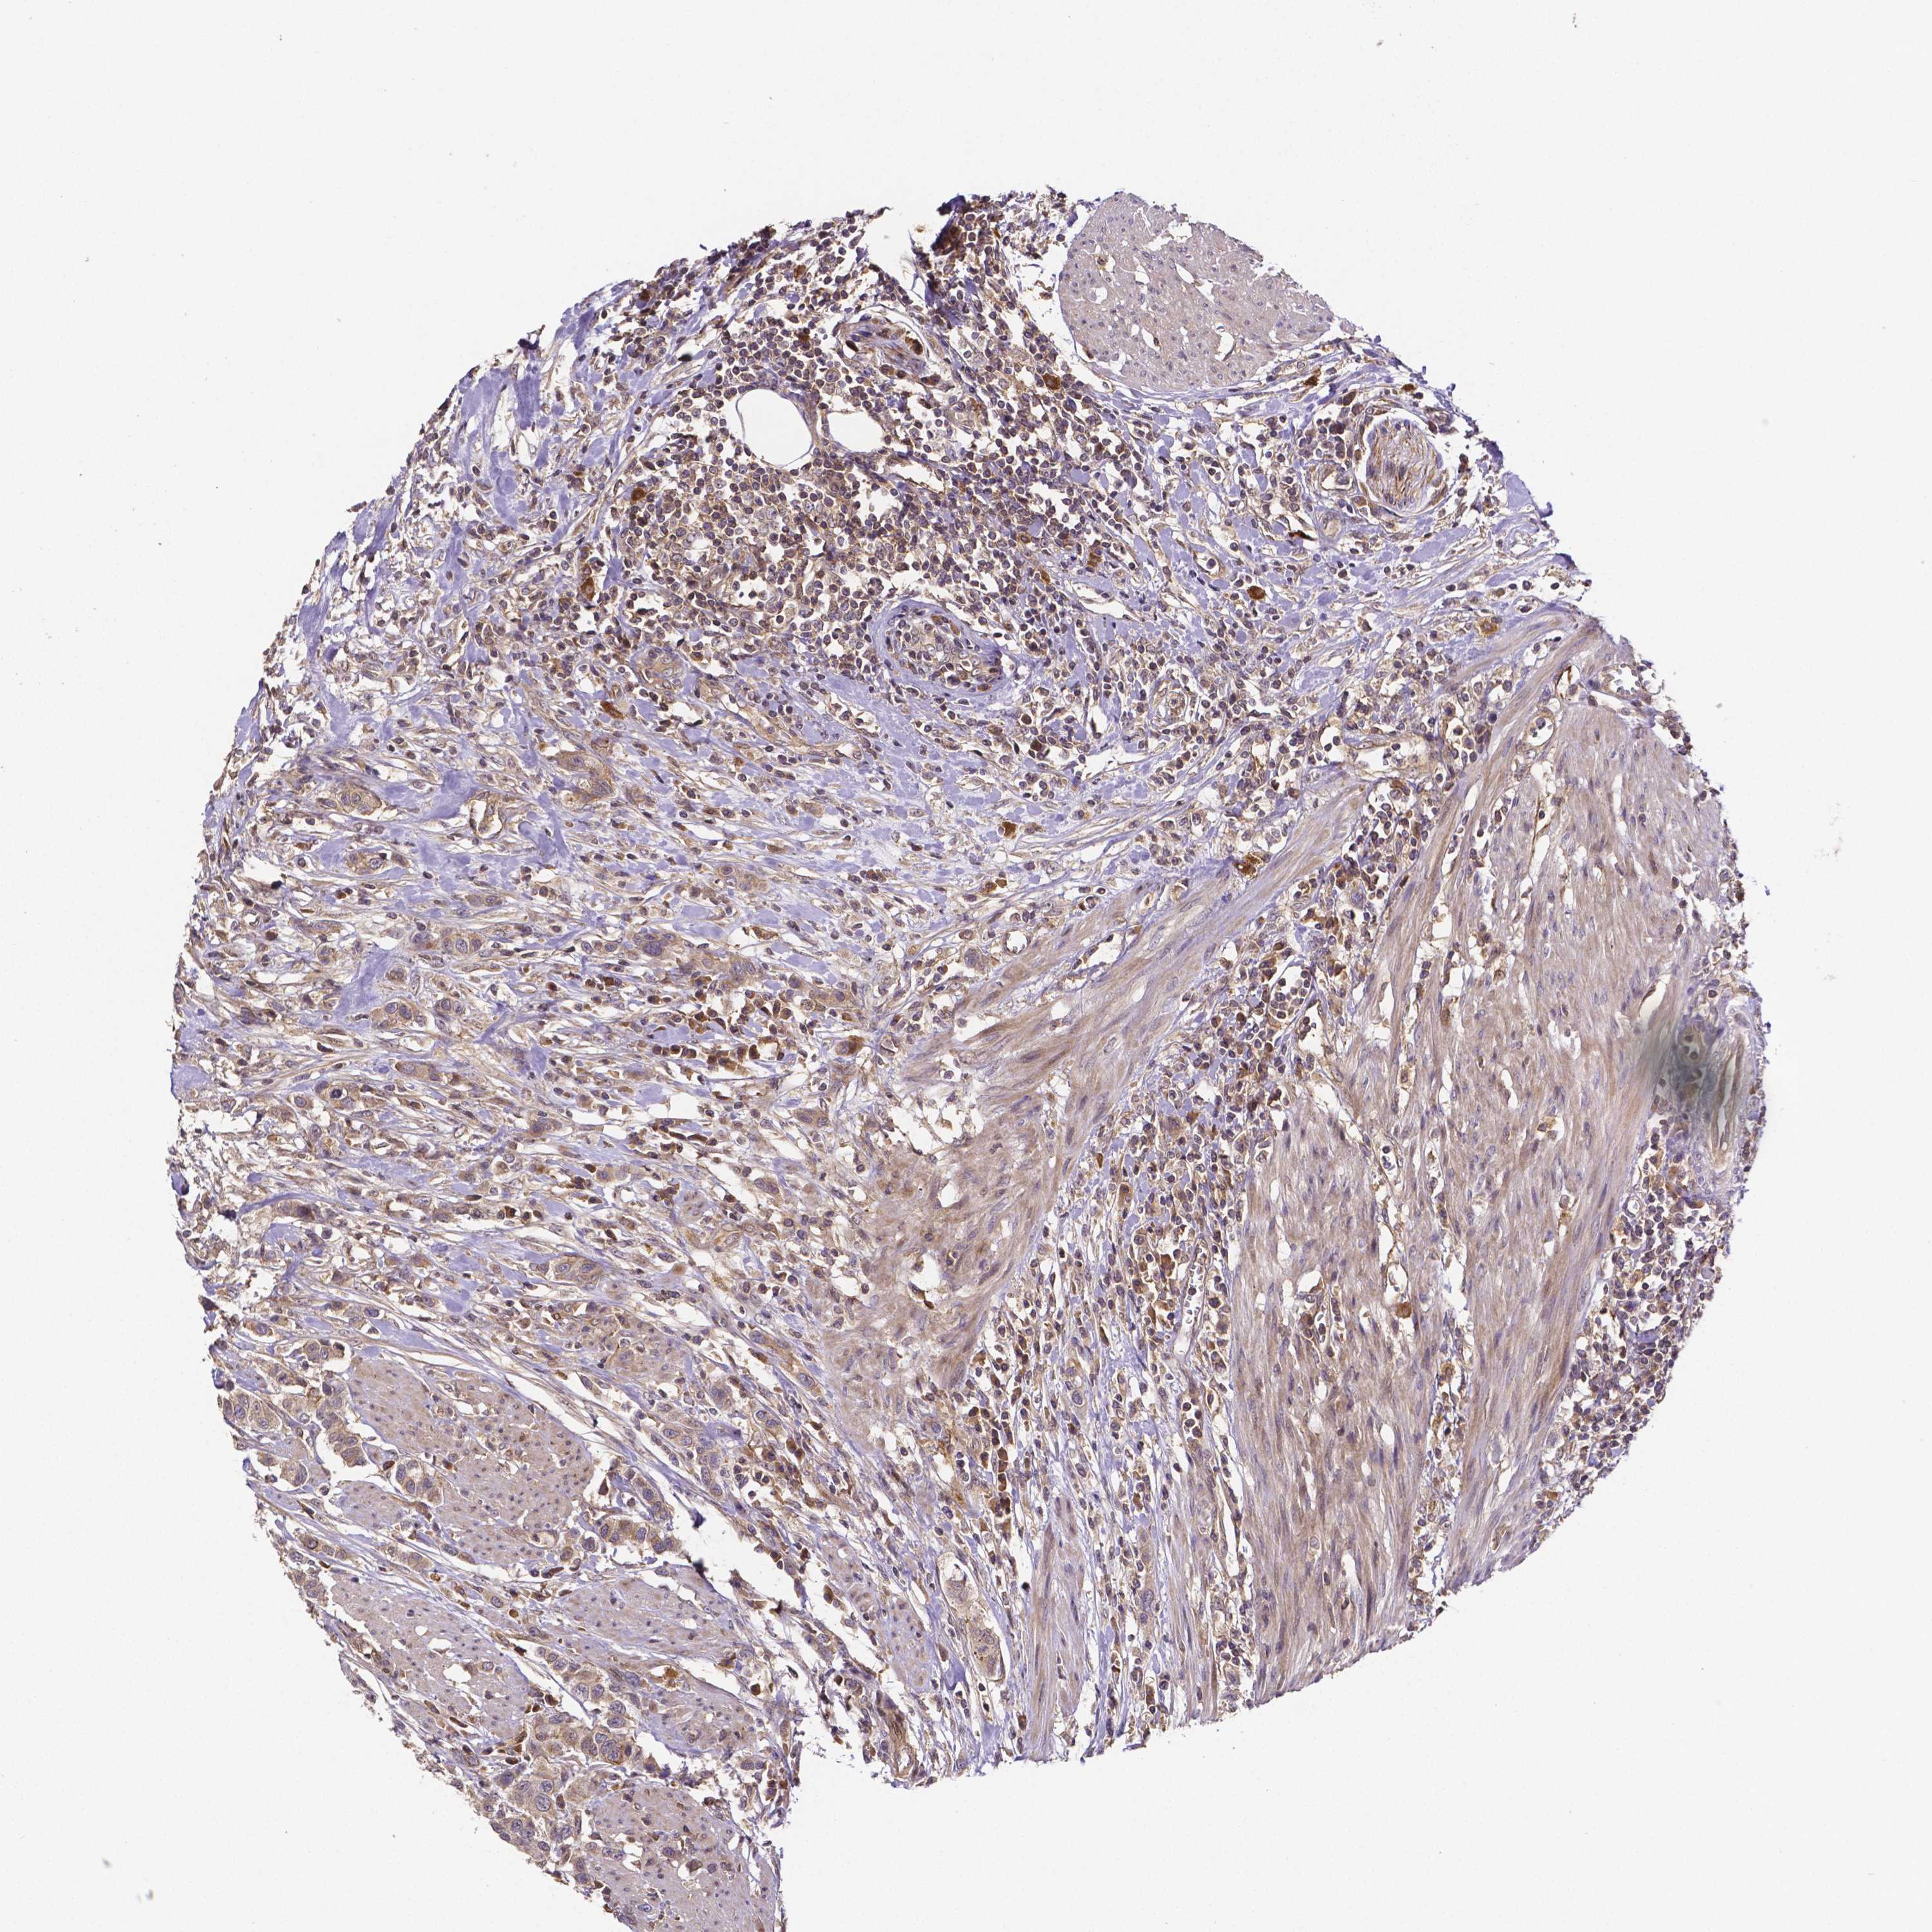

UROTHELIAL CANCER - Protein expressioni

A mouse-over function shows sample information and annotation data. Click on an image to view it in a full screen mode. Samples can be filtered based on level of antibody staining by selecting one or several of the following categories: high, medium, low and not detected. The assay and annotation is described here.

Note that samples used for immunohistochemistry by the Human Protein Atlas do not correspond to samples in the TCGA dataset.

Antibody stainingi

Antibody staining in the annotated cell types in the current human tissue is reported as not detected, low, medium, or high, based on conventional immunohistochemistry profiling in selected tissues. This score is based on the combination of the staining intensity and fraction of stained cells.

Each image is clickable and will lead to virtual microscopy that enables deeper exploration of all samples and also displays staining intensity scores, fraction scores and subcellular localization as well as patient and tissue information for each sample.

Antibody HPA065983

Antibody HPA071879

Urothelial carcinoma, High grade

Urothelial carcinoma, Low grade